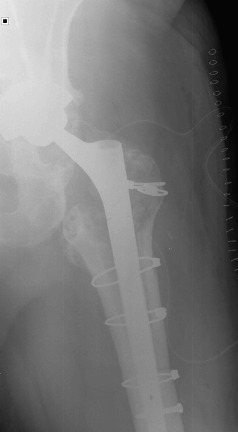

Fig. 4

Fig. 4.

Postoperative radiograph after second revision with four Dall-Milles cerclages.

In October 2013 (two years and one month after the revision procedure), the patient was surprised by a storm and was struck by lightning while strolling. He remained conscious and suddenly he was unable to bear weight on the left leg and a deformity on his left lower extremity was detected. His neurovascular status was stable. Plain radiographs demonstrated a displaced fracture through the base of the neck of the femoral component (Fig. 3 ). The patient underwent revision THA through a posterior iterative approach. A transfemoral osteotomy was required to extract the stem, which presented no signs of loosening. Prophylactic Dall-Miles wiring was done to prevent fractures just under the osteotomy. The selected component for the revision was a modular curve Revitan® (Zimmer, Winterthur, Switzerland) system. It was a 200 × 180 mm stem with a distal locking screw of 36 mm and a metaphysis of 75 mm with 15° of anteversion. The head was a #36 metallic. Finally, the osteotomy was fixed with four Dall-Miles cerclages (Fig. 4 ). After the surgery, the patient needed two blood transfusions due to postoperative anaemia. The postoperative course was otherwise unremarkable and the patient was allowed partial two-crutch assisted weight-bearing. The patient was discharged with an active range of motion of 75° of hip flexion and 15° of hip abduction. Three months after surgery, the radiographs demonstrated consolidation of the osteotomy. After one year, the patient is satisfied, without pain and had returned to work.